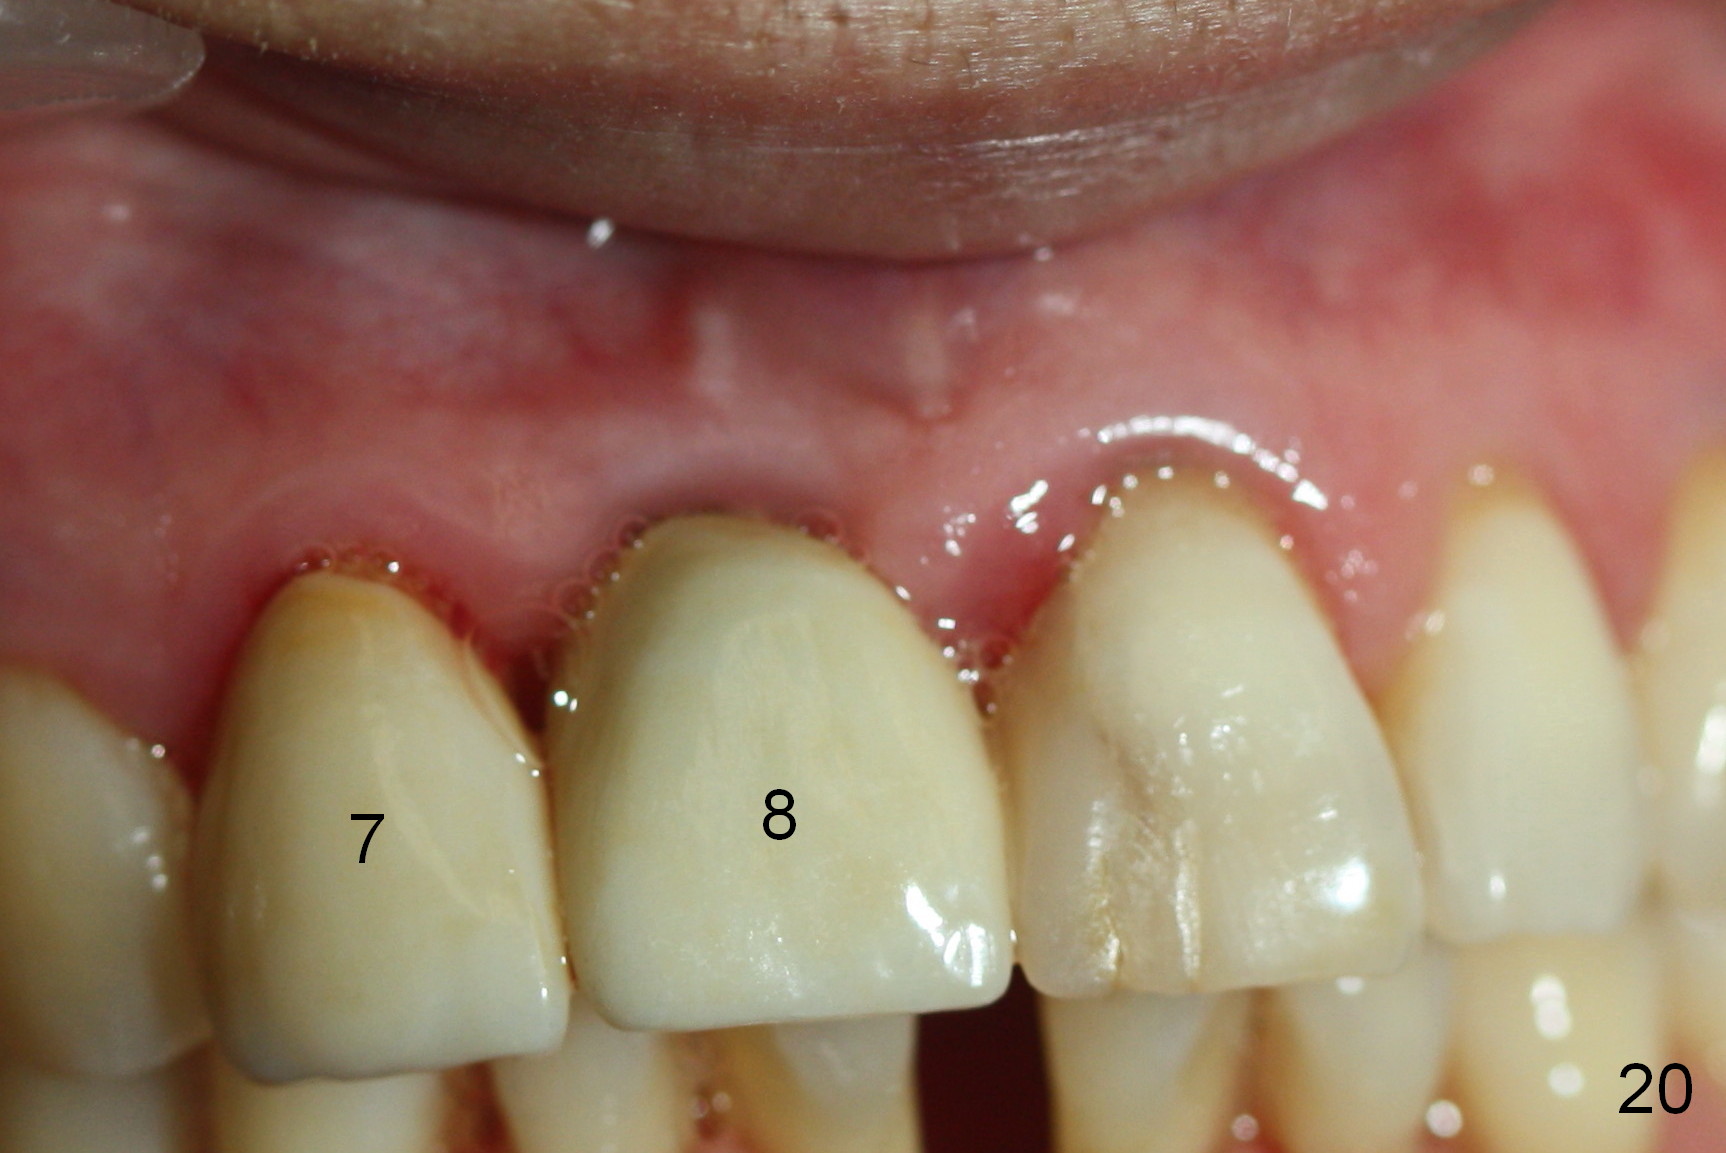

One year post cementation, there is cortical bone formation mesial to the implant (Fig.19 <). Buccal concavity is minimal (Fig.20).